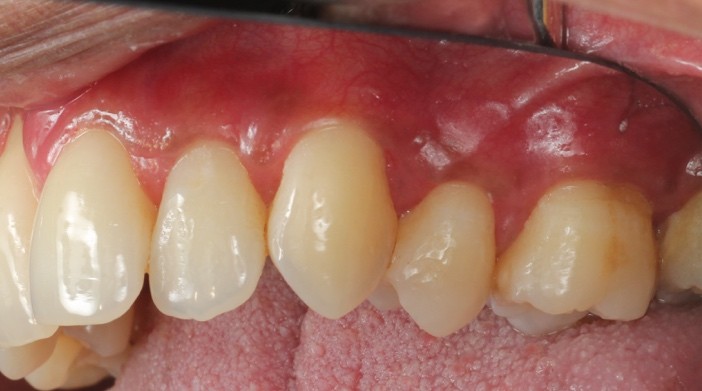

![]() | ![]() |

| Free gingival graft surgery’ to thicken gum and prevent further recession | Gum recession surgery in an aesthetic site |